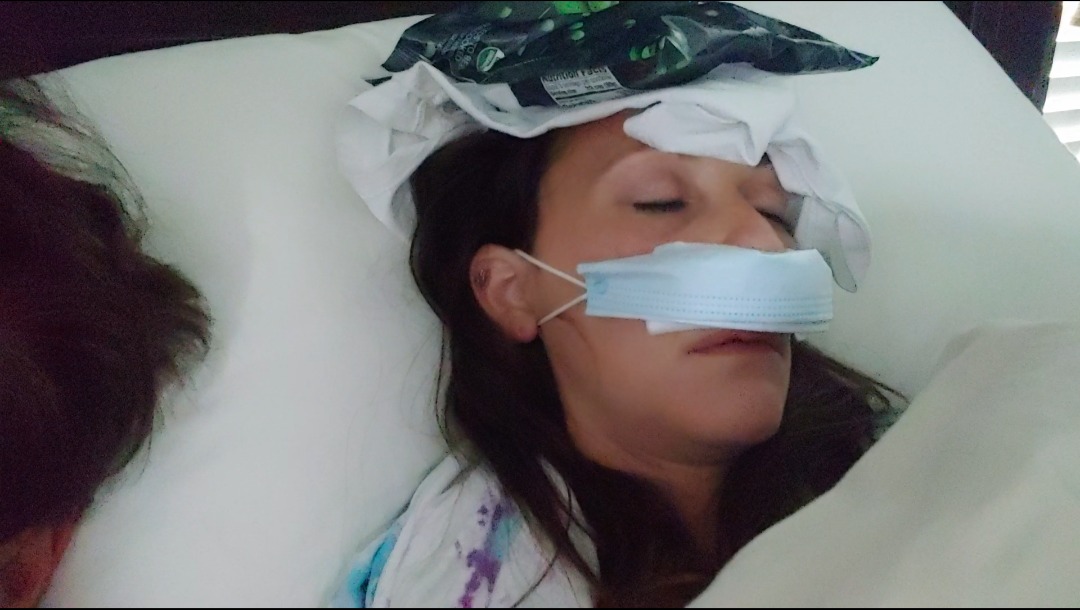

(Some pictures below show a bit of the last 8 months and what "the norm" has become for Kinslee and our family. She continues to have constant bleeding and drainage. Her daily routine involves stuffing her nasal passages with gauze and changing dressings throughout the day. Thank goodness for COVID introducing masks as the norm for some people as it allows her to hide the embarrassment of all this without many second looks from people when out in public)